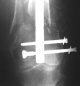

Отправитель: Enes M. Kanlic 13 Ноябрь 2004, 19:43

Dear colleagues,

1. Percutaneous nailing is truly minimally invasive technique, but, unfortunately, nails are not reliable in many hands.

Attached are few examples from our Hospital:

A. Difficult reductions, even in retrograde nailing (my preference, easier control of "small" distal fragment) and it is much, much harder to do it anterograde (Alex, do you have one good case in your collection of anterograde nailing in very distal fractures - as you have suggested that I

should have done it in my previously posted case?

Malpositioning is much too common (recurvatum, varus - valgus).

B. Fixation loosening: distal cutting of the nail, non-unions do happen (cases attached).

Locking Plating has more distal screws than any nail, fixed angles and provides much better fixation, especially in osteoporotic bone.